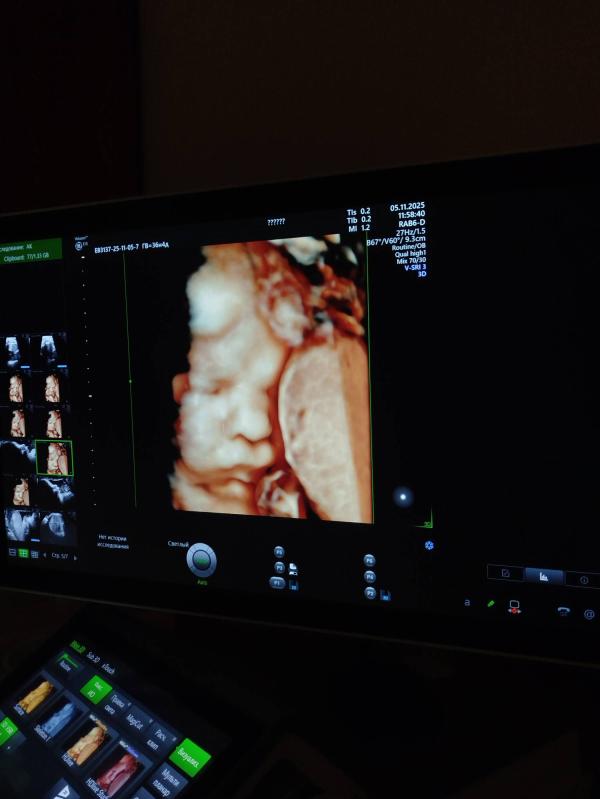

Так же ставят зрп и маловесный плод, но посмотрите на эту бусинку😍

Через 5 дней прием в жк и там решим что делать дальше. Головка прижата, но шейка длинная еще. Ходим🥸 кровотоки в идеале, в целом все хорошо, кроме ог и ож

О, эта дама с трудом далась посмотреть 🤪 сказали в следующий раз прийти на фотометрию если надо будет

Это мое первое УЗИ в 3д, я и не думала, что сделает, потому что шла на обычное😅